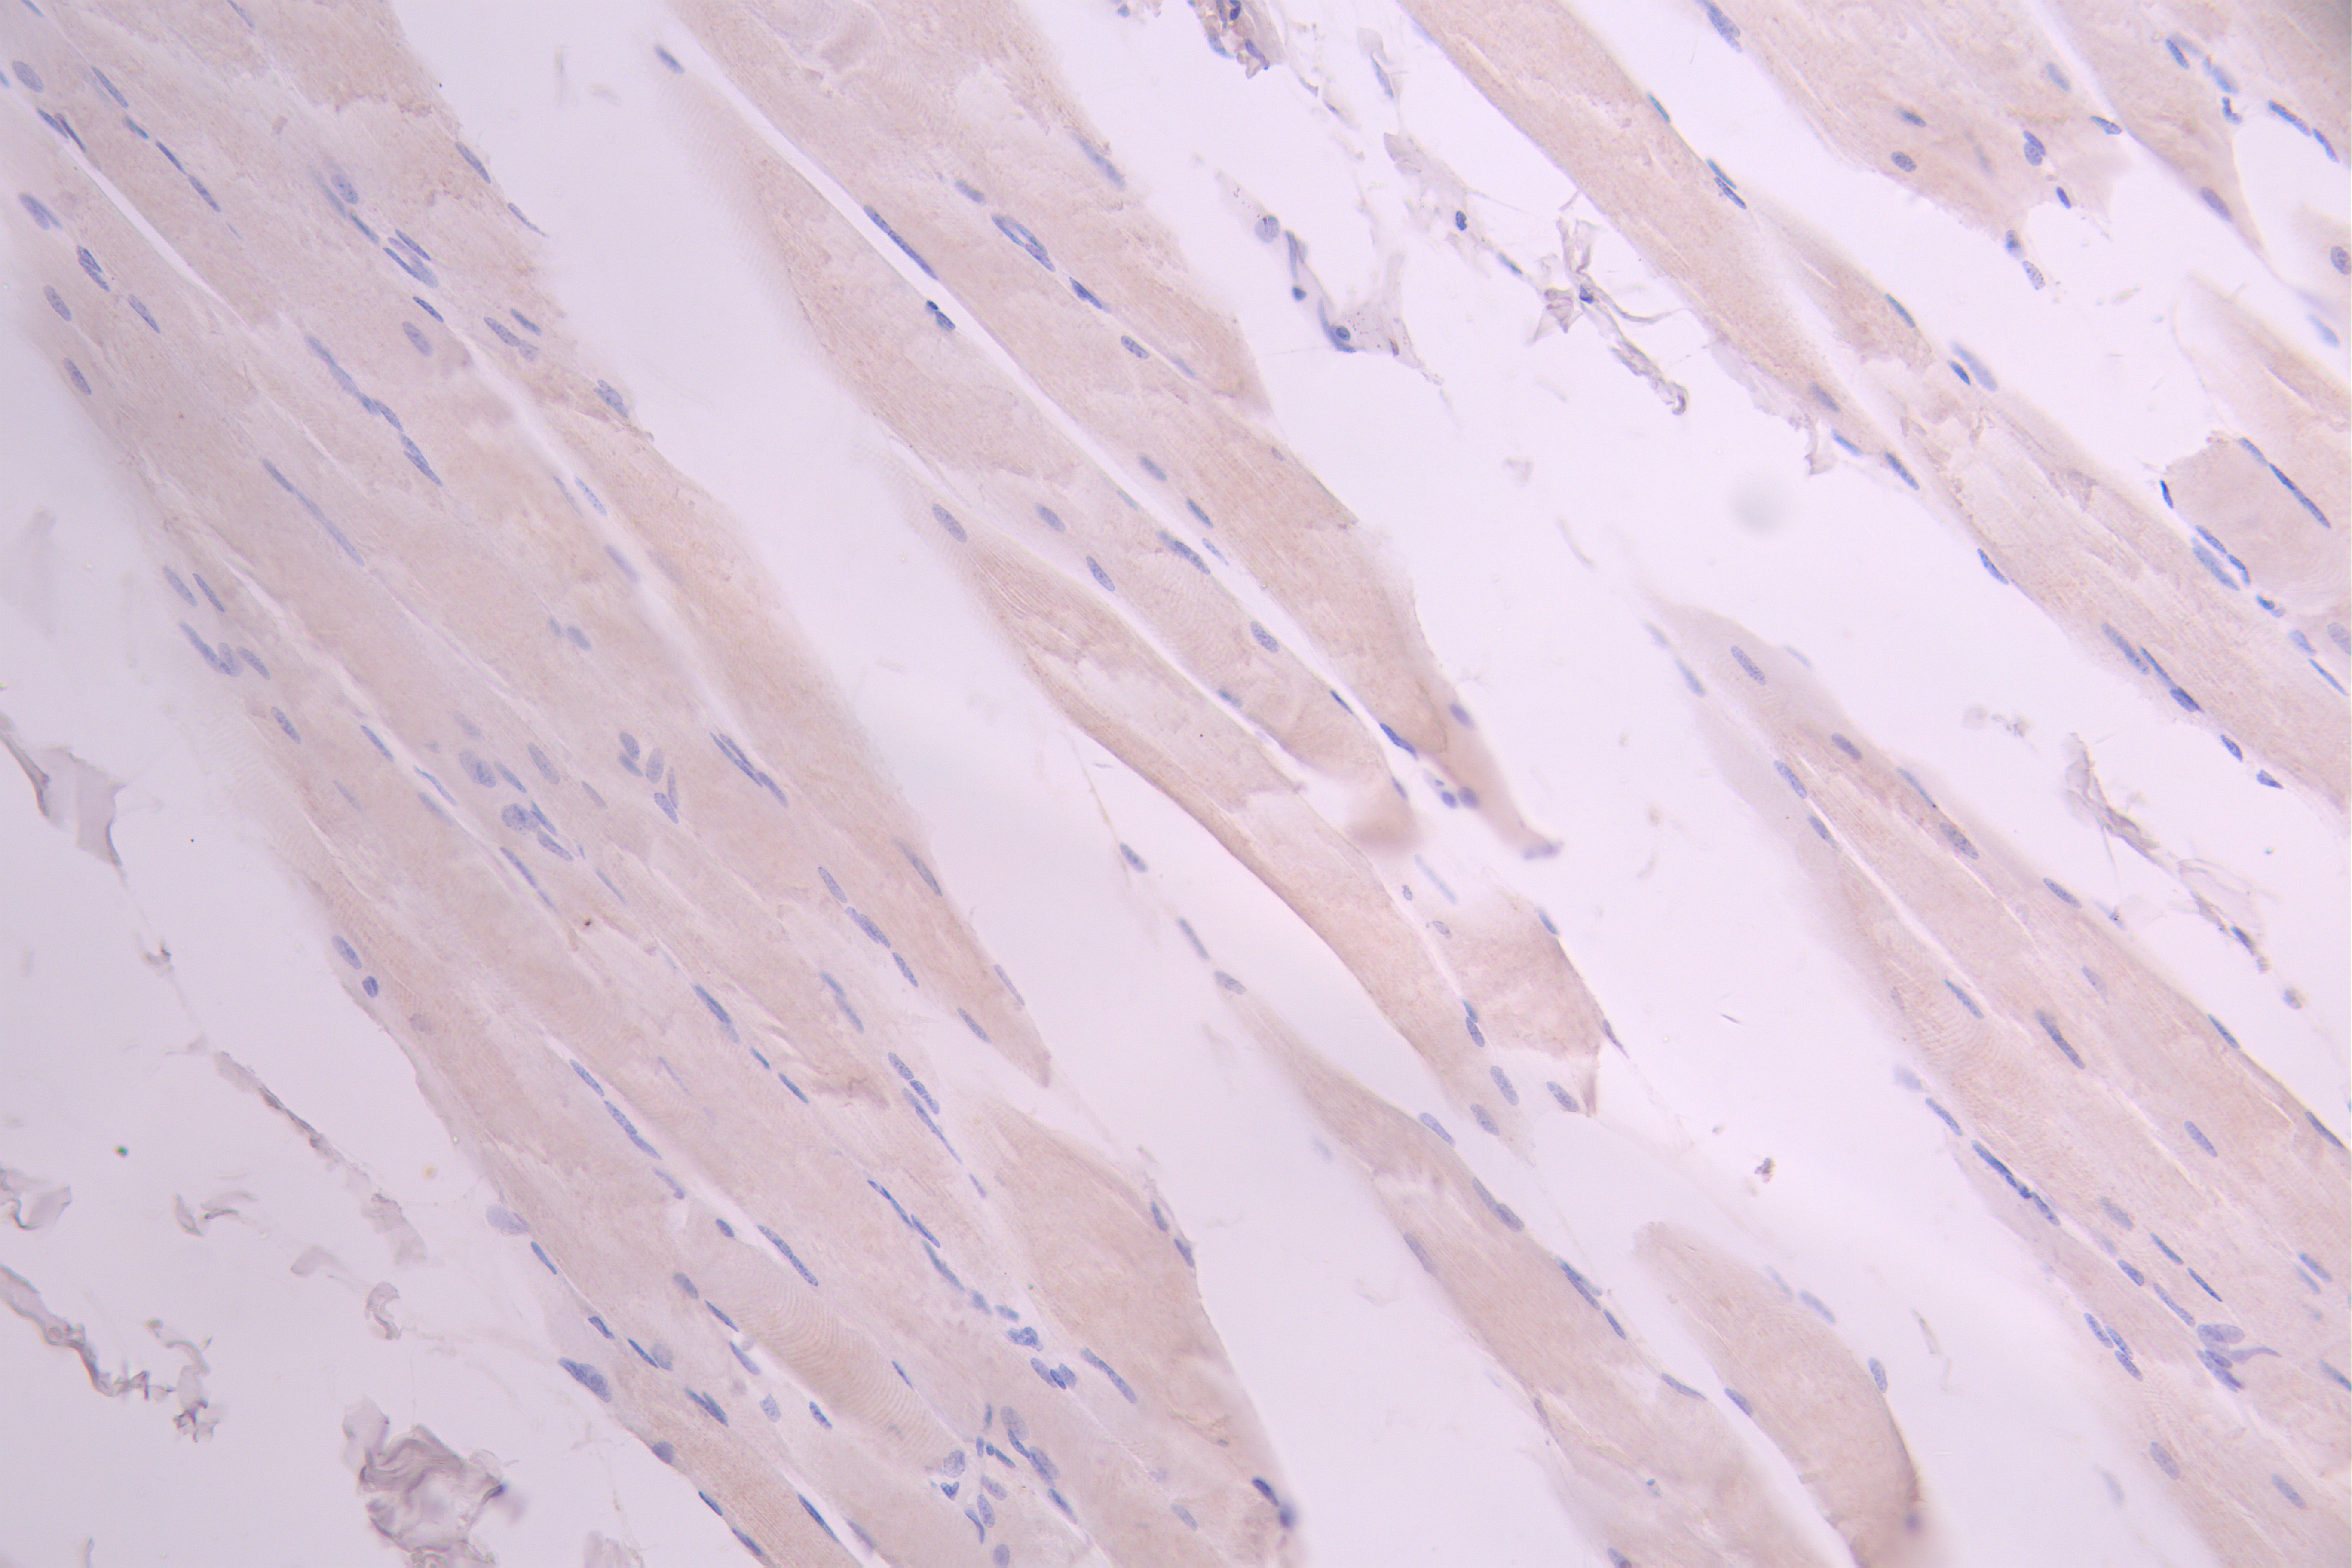

IHC image of CSB-RA025267MA1HU diluted at 1:50 and staining in paraffin-embedded human skeletal muscle tissue performed on a Leica BondTM system. After dewaxing and hydration, antigen retrieval was mediated by high pressure in a citrate buffer (pH 6.0). Section was blocked with 10% normal goat serum 30min at RT. Then primary antibody (1% BSA) was incubated at 4°C overnight. The primary is detected by a Anti-Human lgG, Fcy Fragment Specific labeled by HRP and visualized using 0.05% DAB.